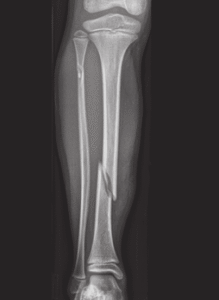

Uma fratura dos ossos da perna ocorre quando há uma quebra em um ou mais ossos que compõem a perna (tíbia e/ou fíbula). A perna é formada por 2 ossos: a tíbia e a fíbula. Esses ossos são essenciais para a mobilidade e a sustentação do peso corporal, e uma fratura pode comprometer seriamente a capacidade de se locomover e realizar atividades diárias.

As fraturas podem variar em gravidade, desde pequenas fraturas (incompletas ou sem desvio) até fraturas complexas (cominutivas) que podem envolver múltiplos fragmentos ósseos. A natureza, a localização e o desvio da fratura e a idade e funcionalidade do paciente da geralmente determinam o tipo de tratamento necessário (conservador ou cirúrgico). É importante entender, entretanto, que uma fratura não se trata apenas de um osso quebrado; ela pode afetar os tecidos circundantes, incluindo músculos, vasos sanguíneos e nervos, aumentando a complexidade do tratamento e da recuperação.

Tipos de fraturas da perna:

As fraturas da perna podem ser classificadas em vários tipos, dependendo da localização, forma e gravidade da fratura. Resumidamentes temos:

Tipo de fratura:

– Transversa

– Obliqua

– Cominuta

As fraturas transversas, por exemplo, são aquelas em que o osso se fratura em uma linha reta através do eixo, frequentemente resultante de um trauma direto. Essas fraturas podem ser relativamente simples de tratar se não houver muitos fragmentos ósseos envolvidos.

Outro tipo comum é a fratura oblíqua, que ocorre em um ângulo ao longo do osso. Essas fraturas podem ser instáveis e frequentemente requerem cirurgia para alinhar e fixar os ossos. As fraturas espirais são causadas por torções, resultando em uma quebra em espiral ao longo do comprimento do osso. Essas fraturas também são geralmente instáveis e podem necessitar de tratamento cirúrgico.

As fraturas cominutivas são aquelas em que o osso se fratura em vários fragmentos, geralmente devido a traumas de alta energia, como acidentes de carro. Essas fraturas são complexas e frequentemente requerem cirurgia e um longo período de recuperação.

Diagnóstico de fraturas da perna:

Após a avaliação clínica, exames de imagem são normalmente utilizados para confirmar a presença e a extensão da fratura. Raios-X são o método mais comum e eficaz para visualizar os ossos e identificar fraturas. Eles fornecem uma imagem clara da localização, tipo e gravidade da fratura, permitindo ao médico planejar o tratamento apropriado. Em casos mais complexos, como fraturas cominutivas ou suspeitas de lesões nos tecidos moles, pode ser necessário o uso de tomografia computadorizada (TC) ou ressonância magnética (RM).